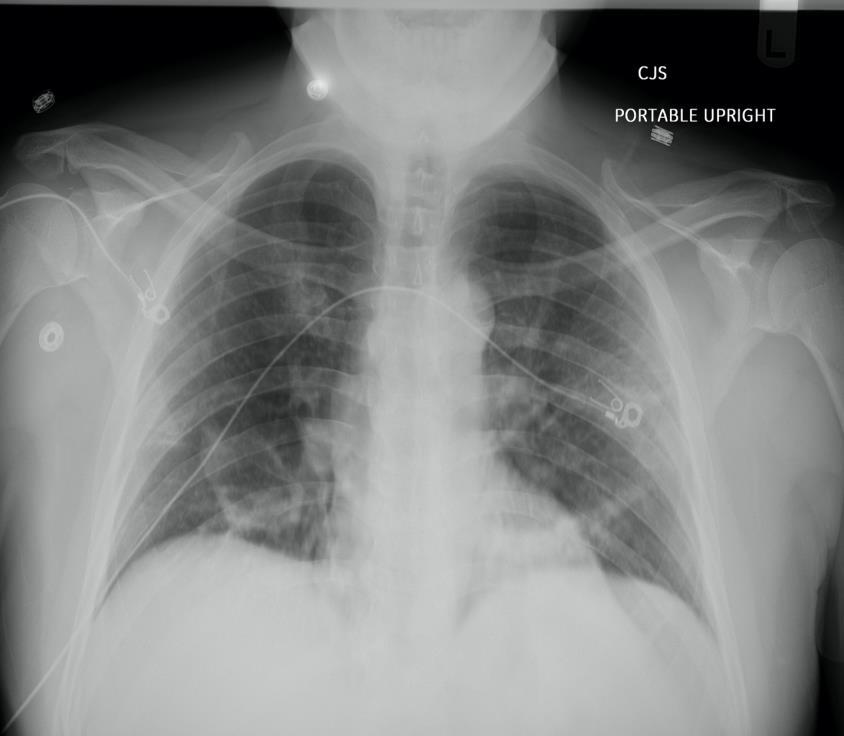

His complete blood count, basic metabolic panel, and venous lactate were baseline for him. His portable chest x-ray is shown.

His chest x ray shows patchy bilateral airspace abnormalities most prominent in the right lower lobe.

Despite albuterol MDI use in the ED, his minor wheezing persisted. He became a bit more tachypneic (28 – 30), but never had O2 saturations below 90%.

Overall, it was felt that he likely had a viral pneumonia based on CXR findings. COVID-19 was presumed, but since it had limited penetration in the local community at that time and nearly 1/3 of viral appearing pneumonias on CXR ultimately have a bacterial cause he received 1 gm ceftriaxone and 500 mg azithromycin, both IV.

Because he was slowly worsening in the ED he was admitted to the hospital. During the five days of his admission he became hypoxic requiring nasal cannula oxygen, but ultimately improved. His COVID-19 testing was positive.